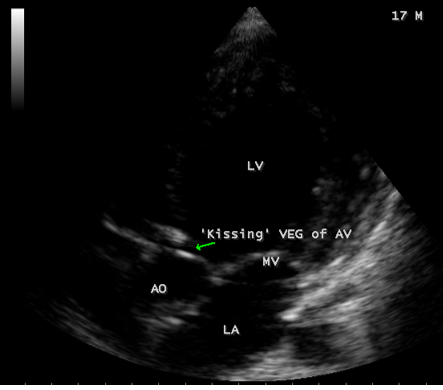

A 17-year-old female was brought to the emergency room with a history of sudden onset of breathlessness. Her pulse rate was 87 bpm and blood pressure 110/60 mmHg. She had a history of rheumatic fever during childhood, an episode of febrile illness for 10 days and taken antibiotic treatment recently. Blood chemistry revealed normal and blood cultures were negative. ECG revealed normal as shown in Figure 1 and X-ray chest revealed dilated LV (left ventricle) as in Figure 2. Physical examination revealed grade 3/6 early diastolic murmur over left mid sternal border, basal crackles over lung fields and no peripheral signs of wide pulse pressure. Transthoracic echocardiography revealed vegetations on anterior and posterior leaflets of aortic valve as in Figure 3 and Figure 4, with a “kissing-type “as in Figures 5, 6 and 8. The aortic valve was bicuspid with an attached vegetation as in Figure 9 and it was severely regurgitant as in Figure 10 and Figure 11. The left ventricle is dilated as in Figure 12 with moderate LV dysfunction as in Figure 13. The thoracic aorta was prominent as in Figure 14 with a ‘holodiastolic flow reversal’ as in Figure 15. The patient was treated with digoxin (0.25 mg, half daily), diuretics (Injection. Furosemide 20 mg IV twice daily), ACE inhibitors (tablet. Enalapril 2.5 mg twice daily) along with 2 weeks course of intravenous (IV) cefotaxime (1g) and amickacin (500mg) twice daily and advised aortic valve replacement at the earliest with lifelong penicillin prophylaxis and continuation of antibiotics for 6 weeks since the vegetations remain stable after 2 weeks of treatment, but without any embolic episodes.

Figure 8: Apical view showing the “ kissing-type” of vegetations (arrow) on the aortic valve in a 17-year old female.

masses with atypical location. Transthoracic echocardiography detects 70% of vegetations > 6 mm and 25% of vegetation < 5>Figures 3 to 9. When endocarditis involves the aortic leaflets, the resultant acute, severe regurgitation as shown in Figures 10, 11 and 15, may often causes dilated left ventricle as in Figure 12 and a prominent aorta as in Figure 14. Secondary infection of mitral valve is a possible finding in primary aortic valve endocarditis. Large aortic valve vegetations (> 6 mm) prolapse into the left ventricular outflow tract and “kiss” the ventricular surface of the anterior mitral leaflet with the development of a vegetation [27],[28],[29]. The left ventricular outflow tract endocarditis may represent the initial site of infection with a possibility to spread by contiguity to both left-sided valves, the mitral and aortic [30], causes the “mitral-kissing vegetation” with a higher prevalence of embolic events [31].